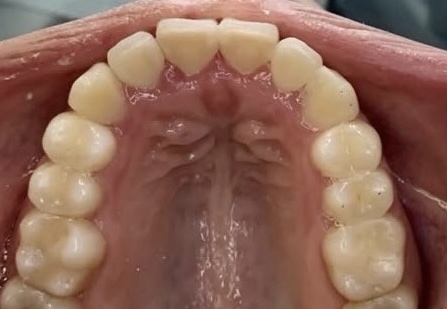

Crowding and constricted arch. Comprehensive orthodontic treatment was performed, and teeth alignment was restored.